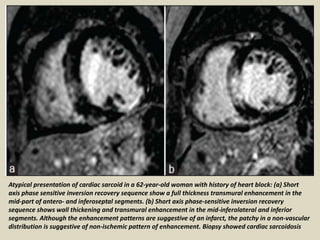

Atypical presentation of cardiac sarcoid in a 62-year-old woman with history of heart block: (a) Short

axis phase sensitive inversion recovery sequence show a full thickness transmural enhancement in the

mid-part of antero- and inferoseptal segments. (b) Short axis phase-sensitive inversion recovery

sequence shows wall thickening and transmural enhancement in the mid-inferolateral and inferior

segments. Although the enhancement patterns are suggestive of an infarct, the patchy in a non-vascular

distribution is suggestive of non-ischemic pattern of enhancement. Biopsy showed cardiac sarcoidosis